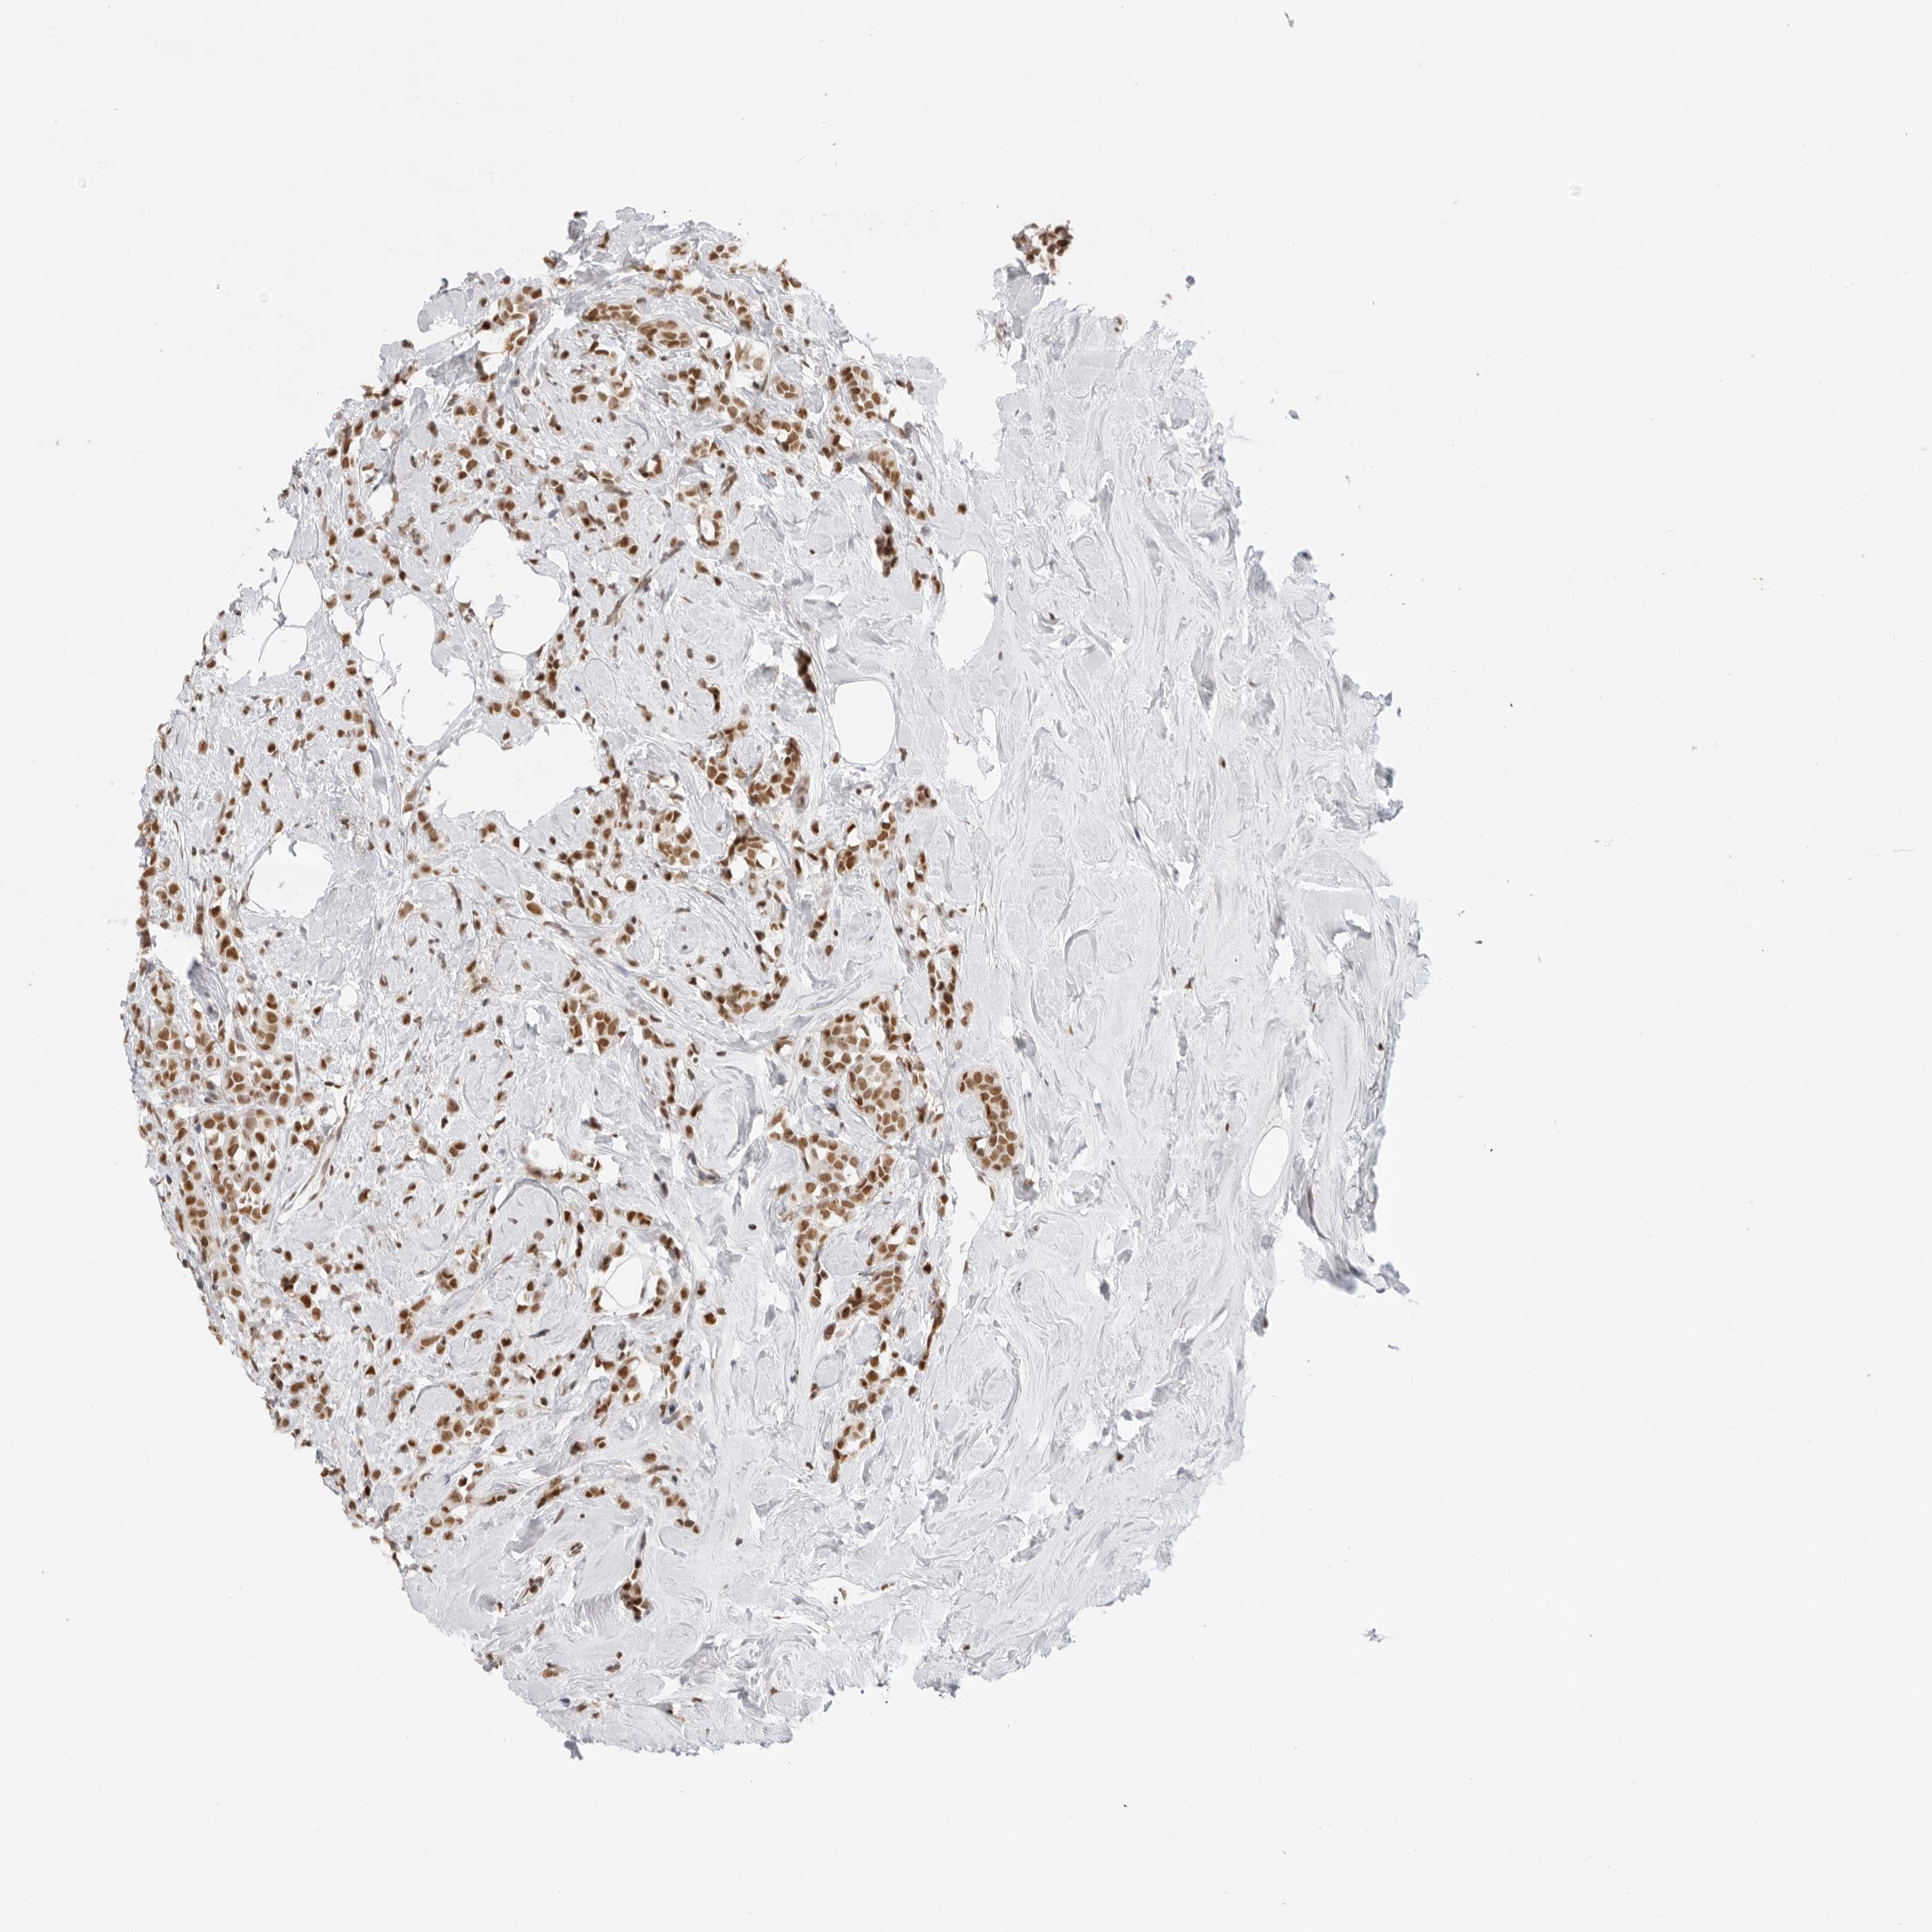

CANCER BREAST CANCER Show tissue menu

BRCA TCGA BRCA VALIDATION PROTEIN EXPRESSION

Breast cancer

Human cancer